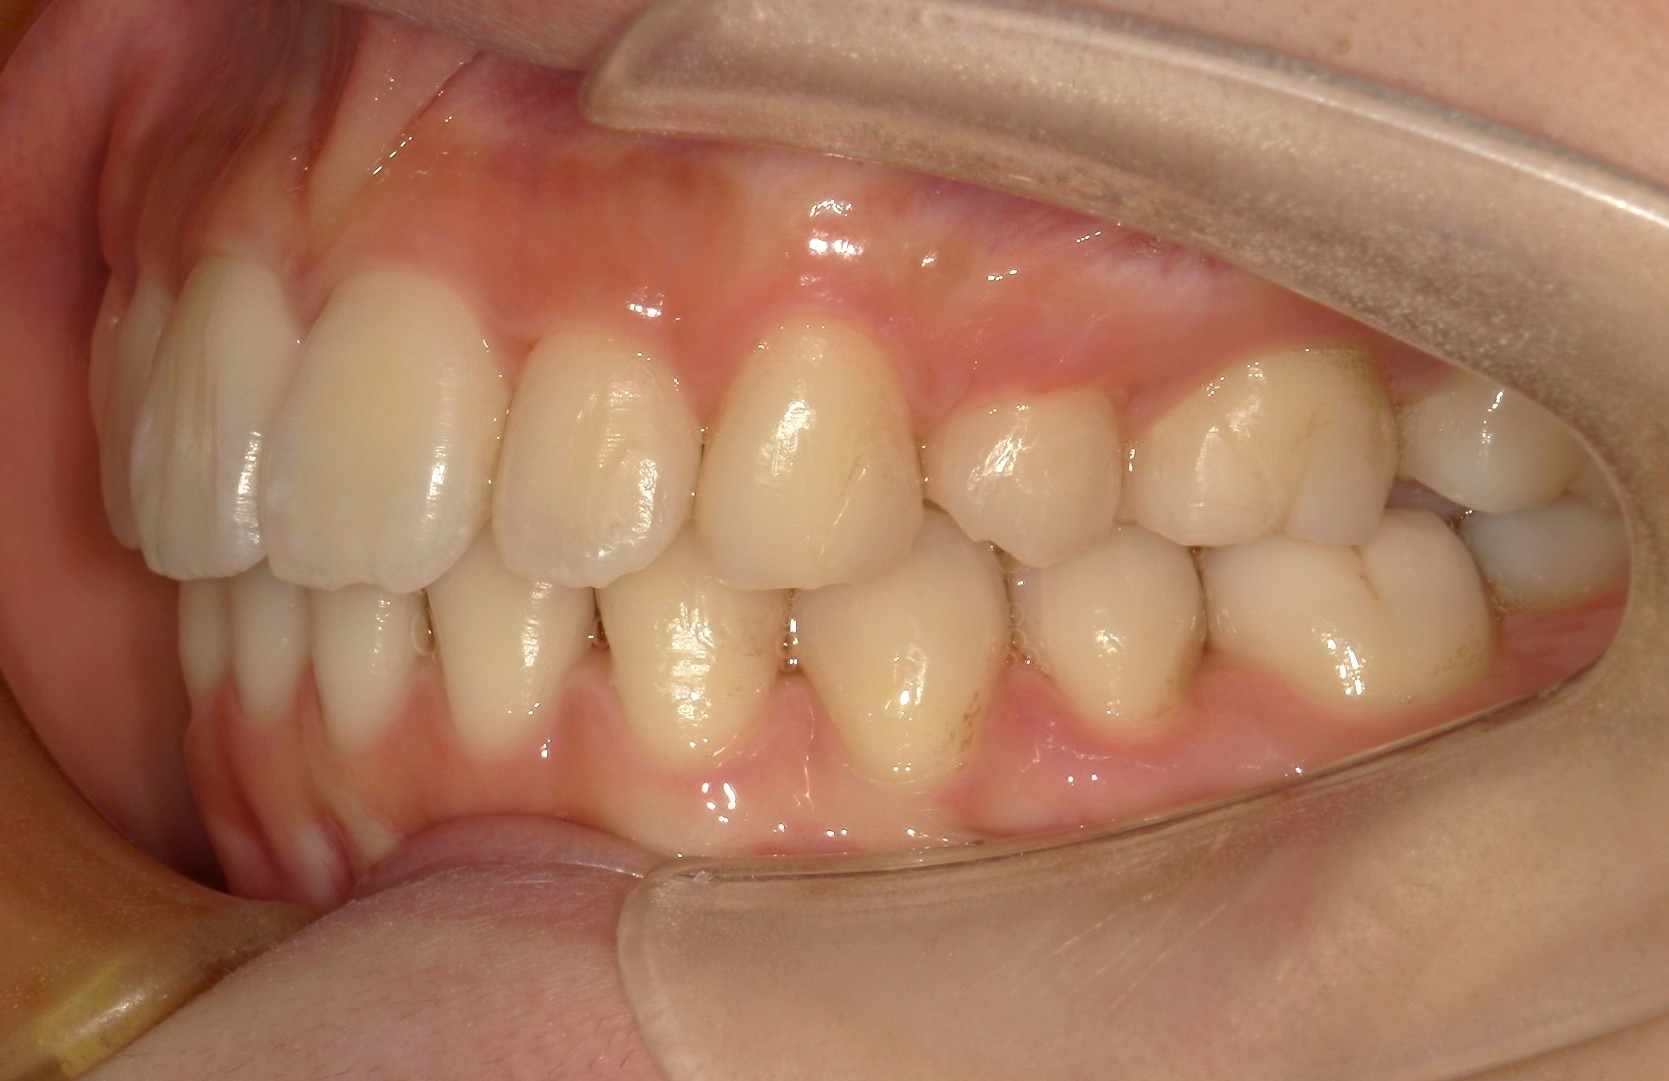

横から見た口腔内写真でよくわかるように、前歯が出っ歯になっており、全く咬んでいない状態でした。また下の前歯が本来4本あるところが、先天的に一本少なく3本しかない(Three incisors)であったため下顎のアーチが小さいというお口の状態でした。前歯を正しい傾きに治し、咬合させるため、上の歯のみ2本の抜歯を行うこととしました。下の前歯が3本のため、その正中に注意しながら前歯の傾きを修正し、奥歯のポジションを整えて仕上げました。口元の突出感は大きく改善し、咬合も良好な状態で完了することができました。

口内右

治療前

治療後